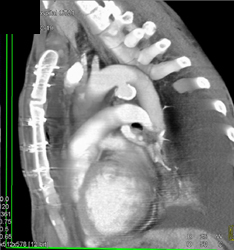

Diagnosis

Ductus Aneurysm